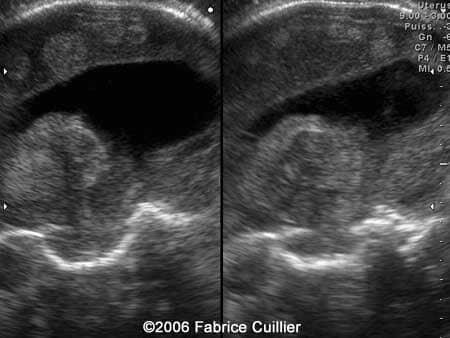

An additional endovaginal scan was performed. There were one large cyst on the right hemisphere and multiple peripheral cysts. The corpus callosum artery was identified. Fetal biometry was in concordance with the gestational age. Karyotyping was offered (46XX). A PCR was performed in the amniotic fluid sample. The result was positive for the Toxoplasma gondii DNA.

Anterior and coronal scan at 30 weeks showing right toxoplasmosis abscess and marked echogenic areas

2

3

Right parasagittal scan at 30 weeks showing ventriculomegaly, echogenic areas and anterior parasagittal marked hyperechogenecity zone

4

5